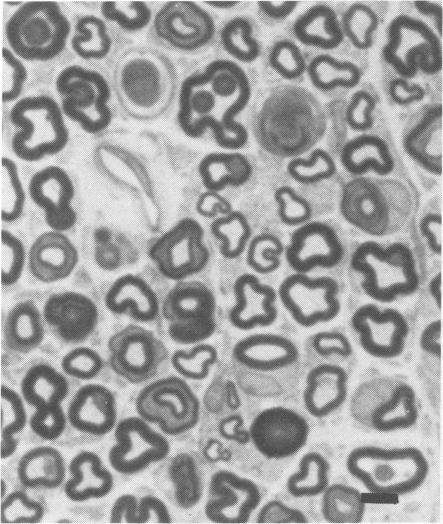

Wistar rats subjected to a single exposure lasting six hours to ethylene oxide (EO) at a concentration of 500 parts per million three times a week for 13 weeks developed ataxia in the hindlegs. Myelinated fibres in hindleg nerves and in the fasciculus gracilis showed axonal degeneration sparing the nerve cell body of the lumbar dorsal root ganglion and myelinated fibres of lumbar dorsal and ventral roots. These pathological findings are compatible with central-peripheral distal axonal degeneration. This is the first animal model of EO neuropathy to be histopathologically verified.

将Wistar大鼠每周三次暴露于浓度为百万分之500的环氧乙烷(EO)中,每次暴露持续6小时,持续13周,大鼠后肢出现共济失调。后肢神经和薄束中的有髓纤维显示轴突变性,而腰背根神经节的神经细胞体以及腰背根和腹根的有髓纤维未受影响。这些病理发现与中枢 - 外周远端轴突变性相符。这是首个经组织病理学证实的EO神经病变动物模型。